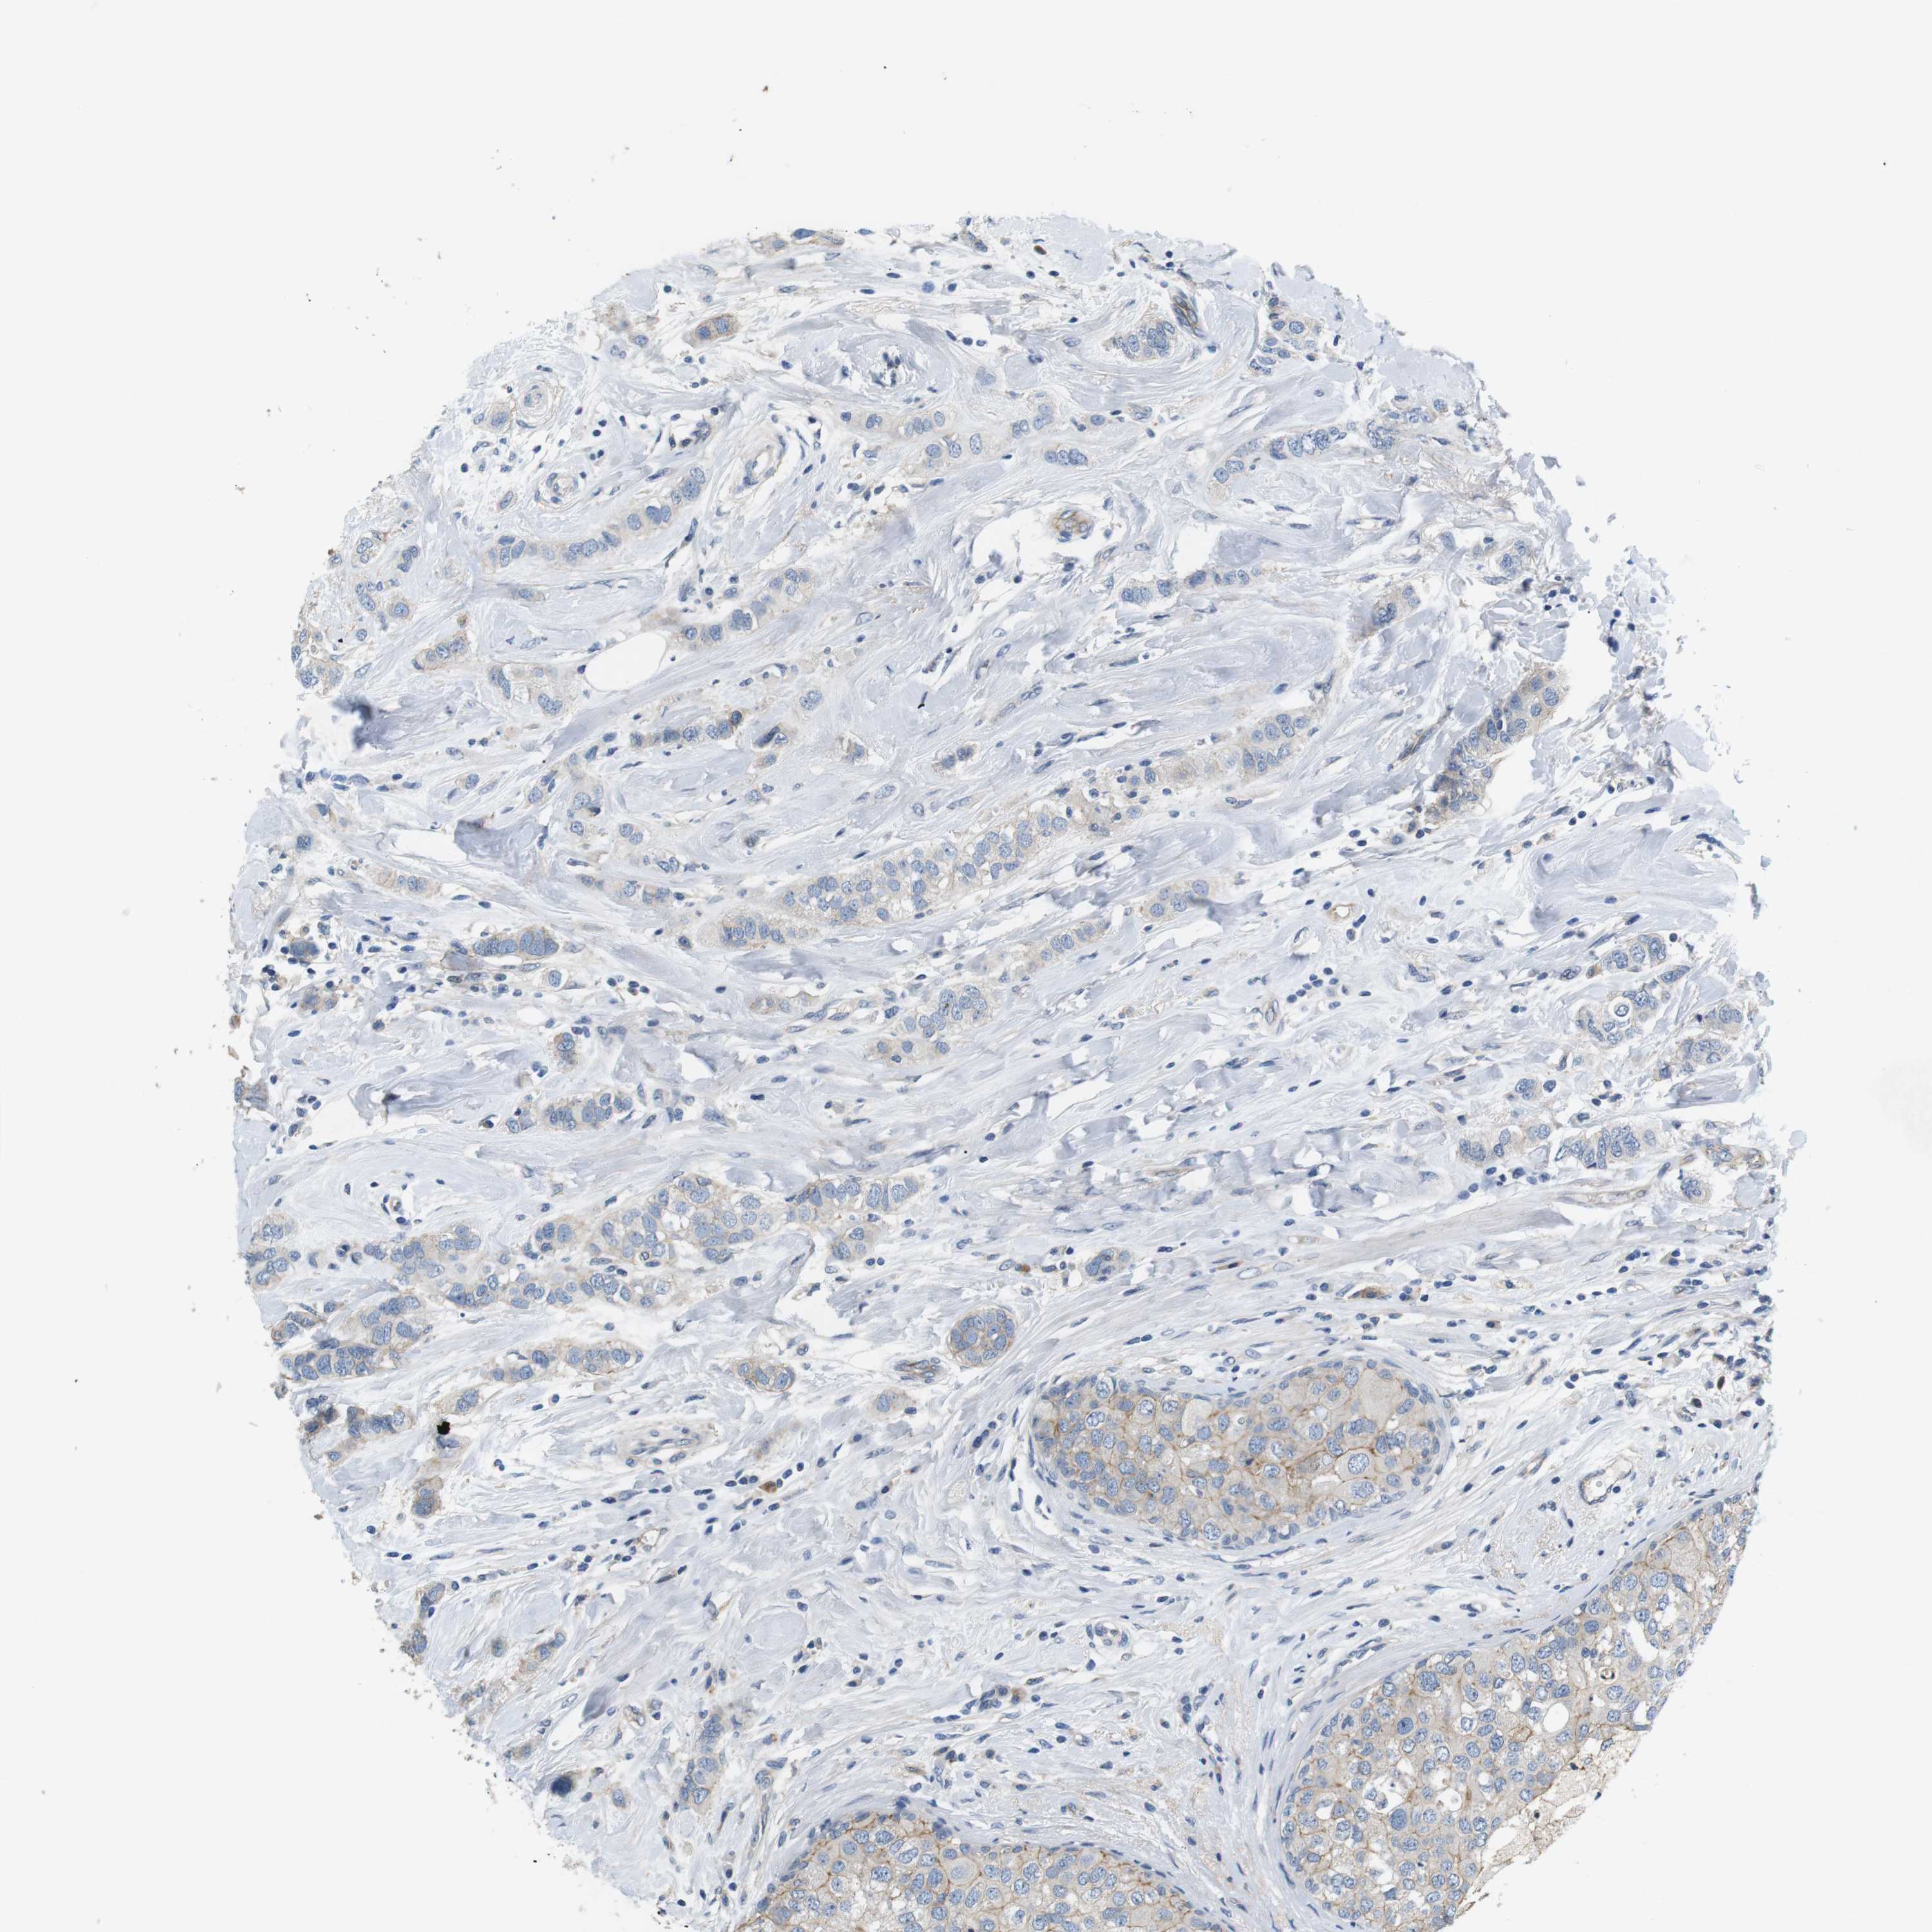

CANCER BREAST CANCER Show tissue menu

BRCA TCGA BRCA VALIDATION PROTEIN EXPRESSION

Breast cancer

Human cancer